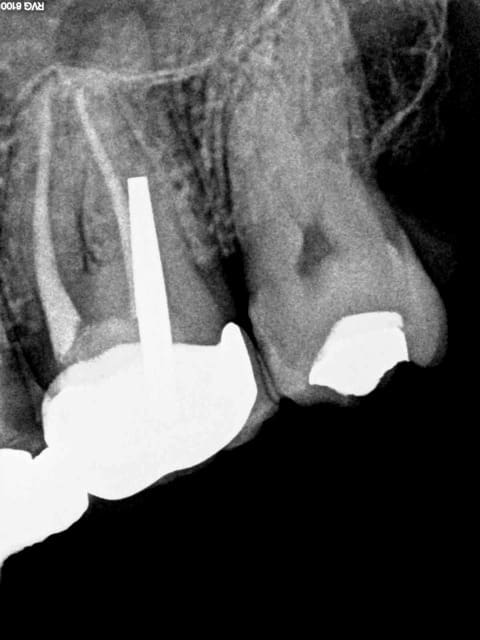

La semaine dernière légère douleur à la percussion sur 27. Et pourtant j'avais vu la radio après endo ! qui était nickel ( ou alors pas les yeux en face des trous ).

Admirez le chef d'oeuvre ! Pas évident de s'auto radiographier !

Quand je dis qu'il faut faire des radios à TOUTES les étapes merde !

c'est le forage pour le pivot qui a retiré tout le traitement de la racine .Il faut aussi une radio pivot en place avant empreinte pour vérifier l'axe . C'est en tout cas ce que je fais car ça m'est déjà arrivé.

Non non non, l'empreinte n'a pas été faite dans la séance de l'endo, c'est pas possible de faire une merde pareille dans ce cas là. Je pige pas. la seule solution c'est qu'il n'a pas obturé le canal volontairement,( palatin en plus) c'est du sabotage. Soit j'ai eu de la merde dans les yeux en voyant la radio post op ( et lui aussi) soit il n'a pas scellé le cone en palatin.

Sans digue, c'est sur mais j'étais consentant. ( amené un optragate, quand meme !) . Le plus dur ? attends qu'on voie si le MV 2 a été traité, j'ai comme un doute.

il a oublié de faire le palatin c'est clair sinon tu aurais des traces de ciment. Pour désobturer je te conseille ultrason start X de maillefer sans eau pointe numero 3 si c'est de la fibre de verre, pointe 4 si c est du métal.

mettre des tenons en Zircone dans des racines tient de la stupidité la plus totale au vu du manque d'élasticité du matériau qui en fatigue cyclique est mauvais pour ce genre de chose.

Et si le canal est obturé au ciment de scellement, c'est pas radio opaque, et t'auras fait tout ça pour rien.

En même temps tu le sauras que quand t'auras fait enlever le tenon.